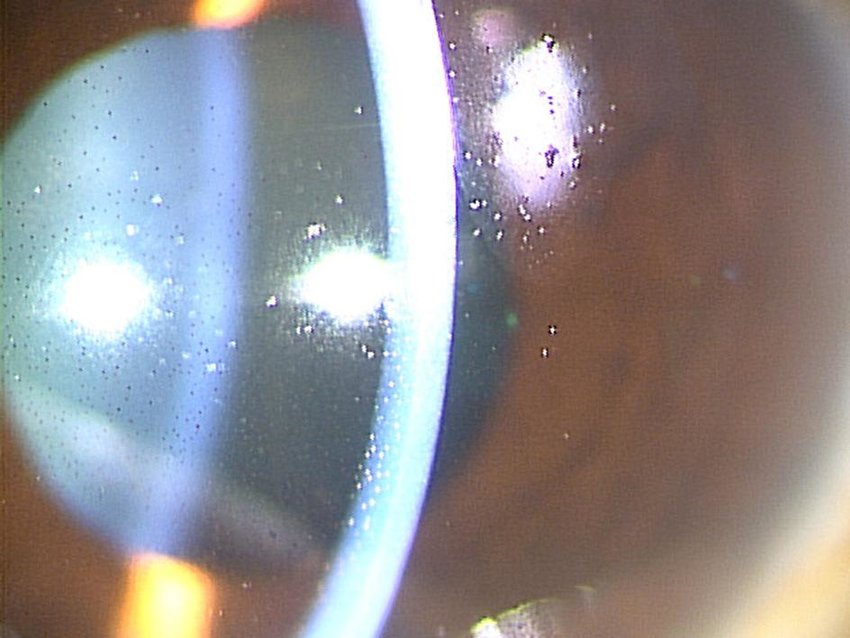

<감압망막병증(ocular decompression retinopathy)>

감압망막병증이란,

수술전 안압이 높던 환자에서 녹내장 수술이후 안압이 갑자기 떨어지면서,

안구내에서 출혈이 발생하는 경우를 의미합니다.

술전 안압이 매우 높았던 경우에서 수술후 갑자기 안압이 훅떨어지게되면,

시신경 유두부위에서 눌리고, 밀려있던 사상판이

안구내쪽으로 빨려들어오는 형태변화가 발생합니다.

이로인해서 시신경유두주위에 있던 망막 정맥이 폐쇄되면서

망막정맥폐쇄가 발생하는 현상입니다.

소아에서 더잘 발생한다고 알려져 있습니다.